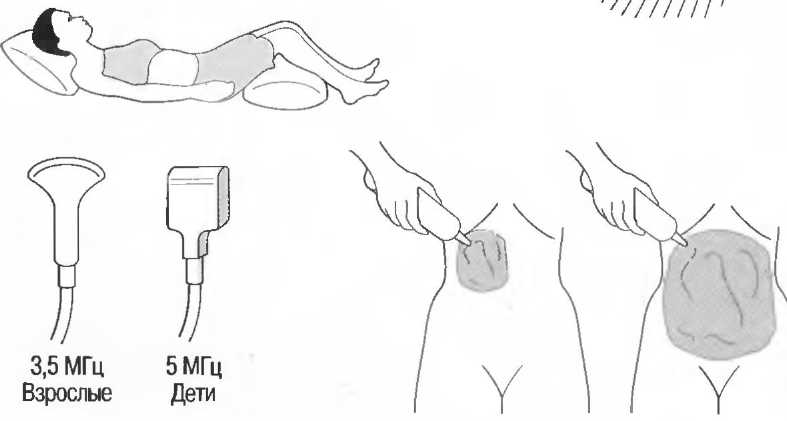

Аорту и нижнюю полую вену. |

|

2. |

Печень, воротную вену, печеночные вены. |

|

3. |

Желчевыводящие пути и желчный пузырь. |

|

4. |

Селезенку. |